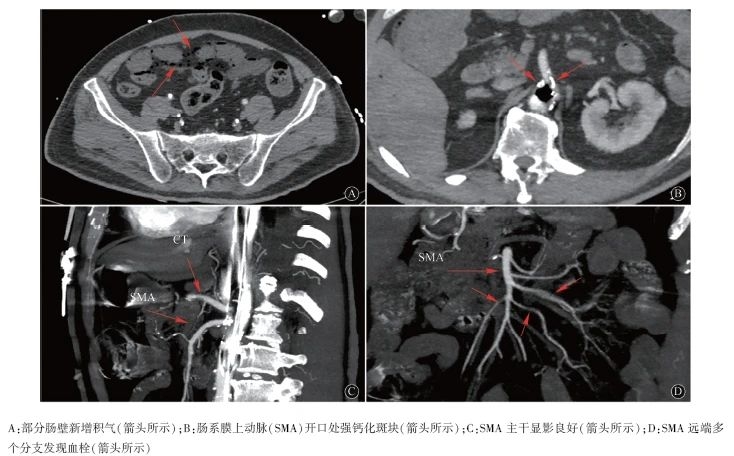

患者持续IABP辅助循环,并以肝素持续静脉泵入抗凝治疗,同时动态监测凝血功能。在患者家属考虑下一步治疗方案期间,患者出现进食后呕吐及脐周绞痛等消化道症状,疼痛较剧烈,间断缓解。为排除胰腺炎、缺血性肠病(ischemic bowel disease,IBD)等急腹症,查血浆D-二聚体3.38 mg/L,大血管增强CT示肠系膜上动脉(superior mesenteric artery,SMA)、双侧髂动脉、双下肢动脉、降主动脉、腹主动脉多发钙化斑块及狭窄、腹主动脉和双侧髂总动脉多发穿透性溃疡,床旁肝胆胰脾彩超、血浆淀粉酶、脂肪酶未见明显异常。经消化科及心外科会诊,考虑患者腹痛可能由胃肠痉挛及腹主动脉溃疡引起,但不排除IBD可能,建议继续动态观察明确病因,给予护胃、解痉、降压、稳定心率等治疗后症状稍缓解。植入IABP后第3天(2月12日),患者再诉腹痛,查体:腹肌紧张,上腹深压痛,无反跳痛,肠鸣音明显减弱,为排除IBD复查大血管增强CT示肝内、门脉系统、腹腔、部分肠壁、肠系膜上静脉新增大量积气,SMA开口处强钙化斑块,SMA主干显影良好,SMA远端多个分支发现血栓(图1),查部分凝血活酶时间(APTT)35.9 s(参考值23.9~31.9 s),D-二聚体26.7 mg/L,血红蛋白137 g/L,白细胞15.53×109/L,血小板77×109/L。

图1 患者腹部增强CT